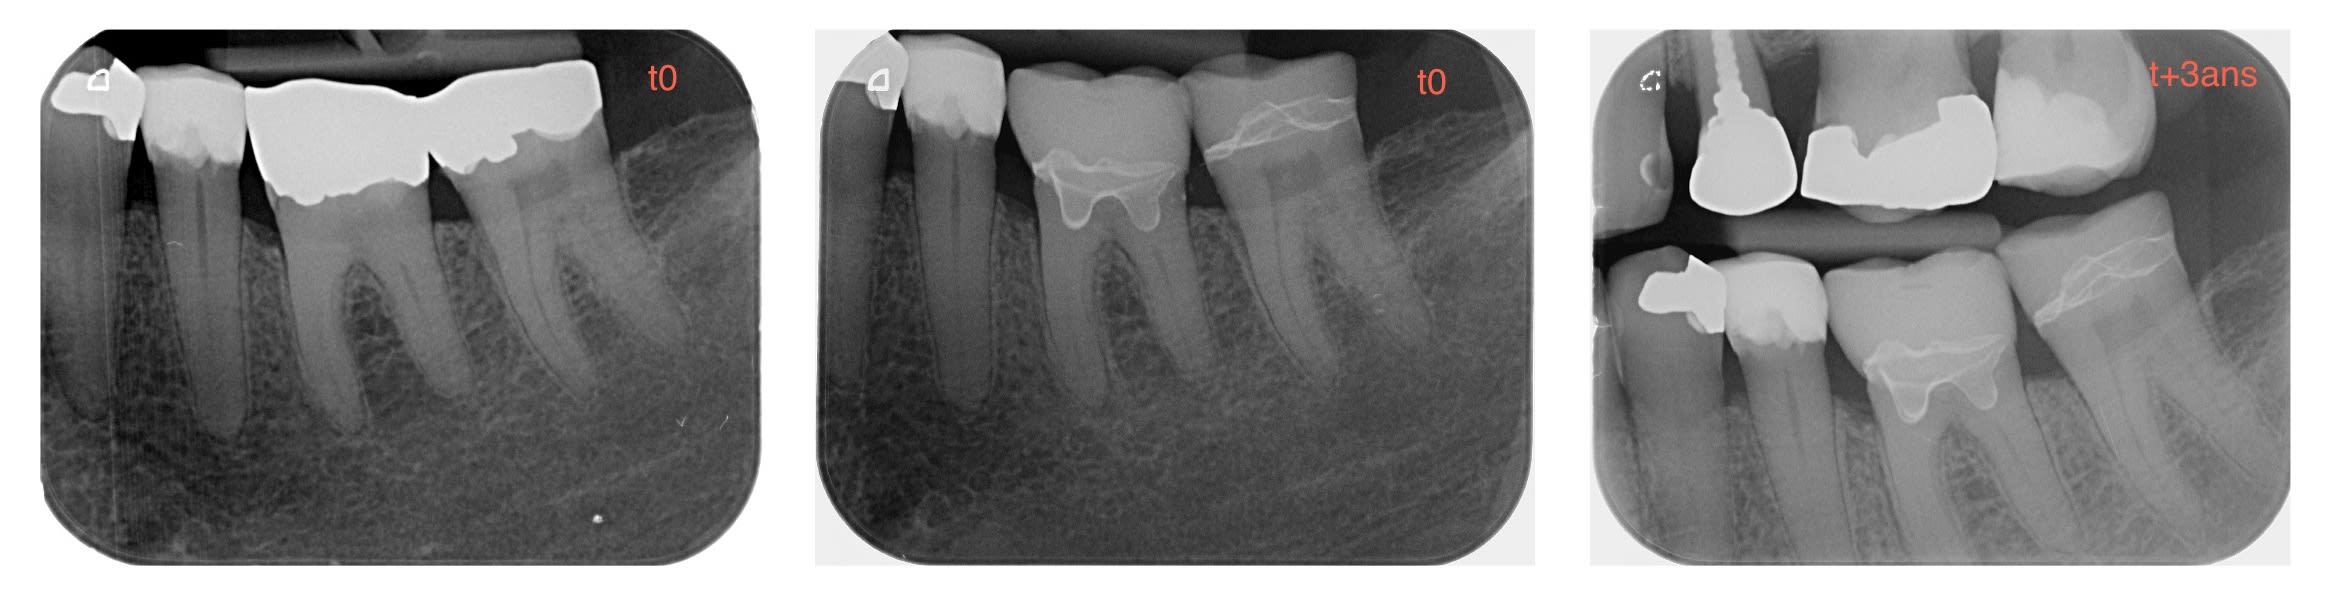

Je ne fais jamais d'endo-couronne, mais dans ce cas précis, après ablation de l'amg et curetage des tissus cariés, la dent conservé une vitalité +.

j'ai donc tenté une endo-couronne, mais sur dent vivante, Emax collée au variolink.

A 3 ans, vit +, et ras.

Comme quoi, il faut faire preuve d'imagination quelquefois, et de prise de risque.